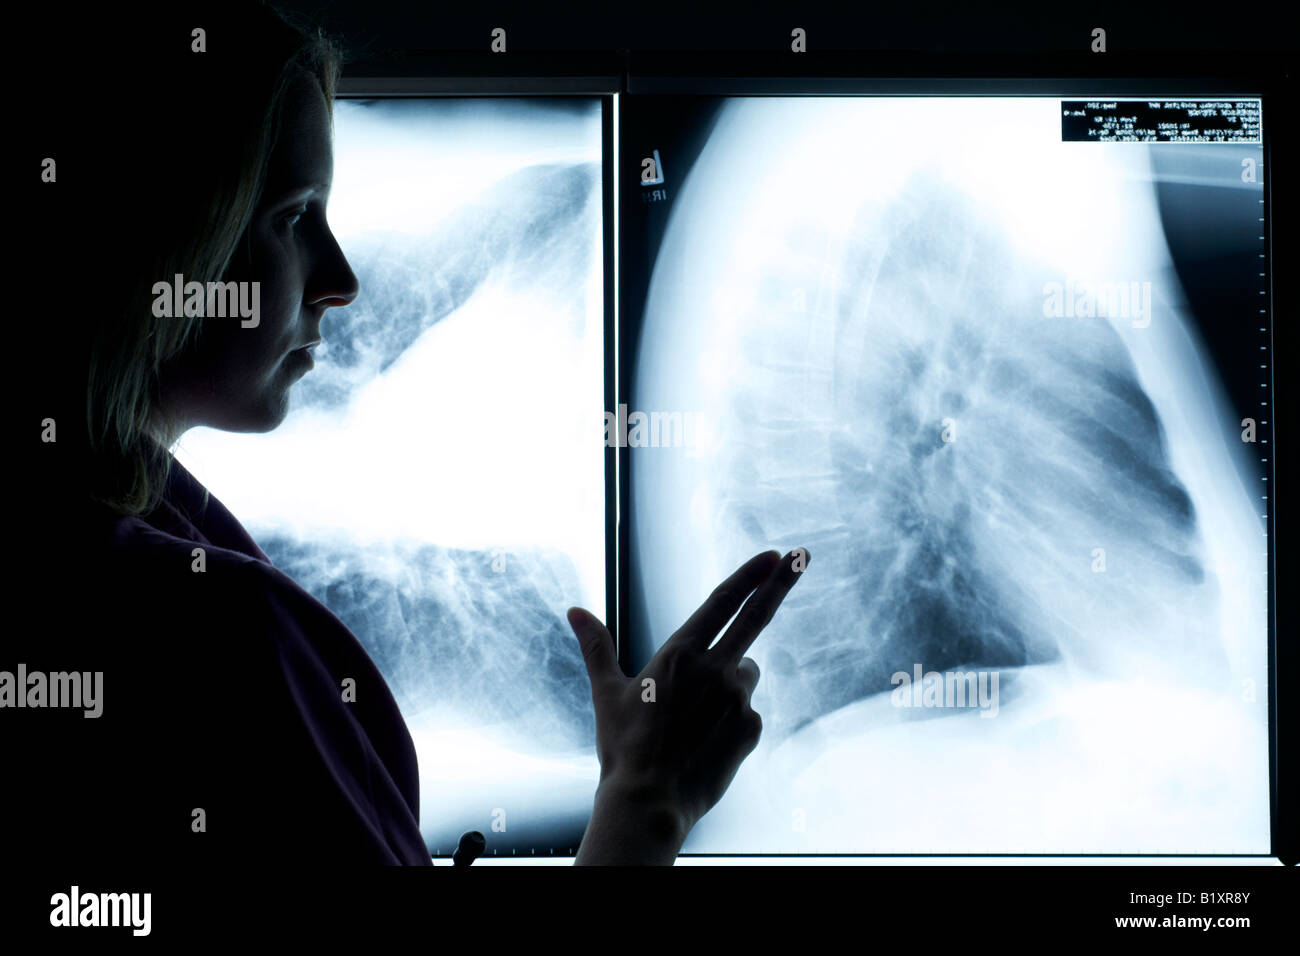

Dans scrubs infirmier stéthoscope avec examen de Xray. Silhouette shot. Banque D'Imageshttps://www.alamyimages.fr/image-license-details/?v=1https://www.alamyimages.fr/photo-image-dans-scrubs-infirmier-stethoscope-avec-examen-de-xray-silhouette-shot-18419876.html

Dans scrubs infirmier stéthoscope avec examen de Xray. Silhouette shot. Banque D'Imageshttps://www.alamyimages.fr/image-license-details/?v=1https://www.alamyimages.fr/photo-image-dans-scrubs-infirmier-stethoscope-avec-examen-de-xray-silhouette-shot-18419876.htmlRFB1Y2MM–Dans scrubs infirmier stéthoscope avec examen de Xray. Silhouette shot.

Dans scrubs infirmier stéthoscope avec examen de Xray. Silhouette shot. Banque D'Imageshttps://www.alamyimages.fr/image-license-details/?v=1https://www.alamyimages.fr/photo-image-dans-scrubs-infirmier-stethoscope-avec-examen-de-xray-silhouette-shot-18414059.html

Dans scrubs infirmier stéthoscope avec examen de Xray. Silhouette shot. Banque D'Imageshttps://www.alamyimages.fr/image-license-details/?v=1https://www.alamyimages.fr/photo-image-dans-scrubs-infirmier-stethoscope-avec-examen-de-xray-silhouette-shot-18414059.htmlRFB1XR8Y–Dans scrubs infirmier stéthoscope avec examen de Xray. Silhouette shot.